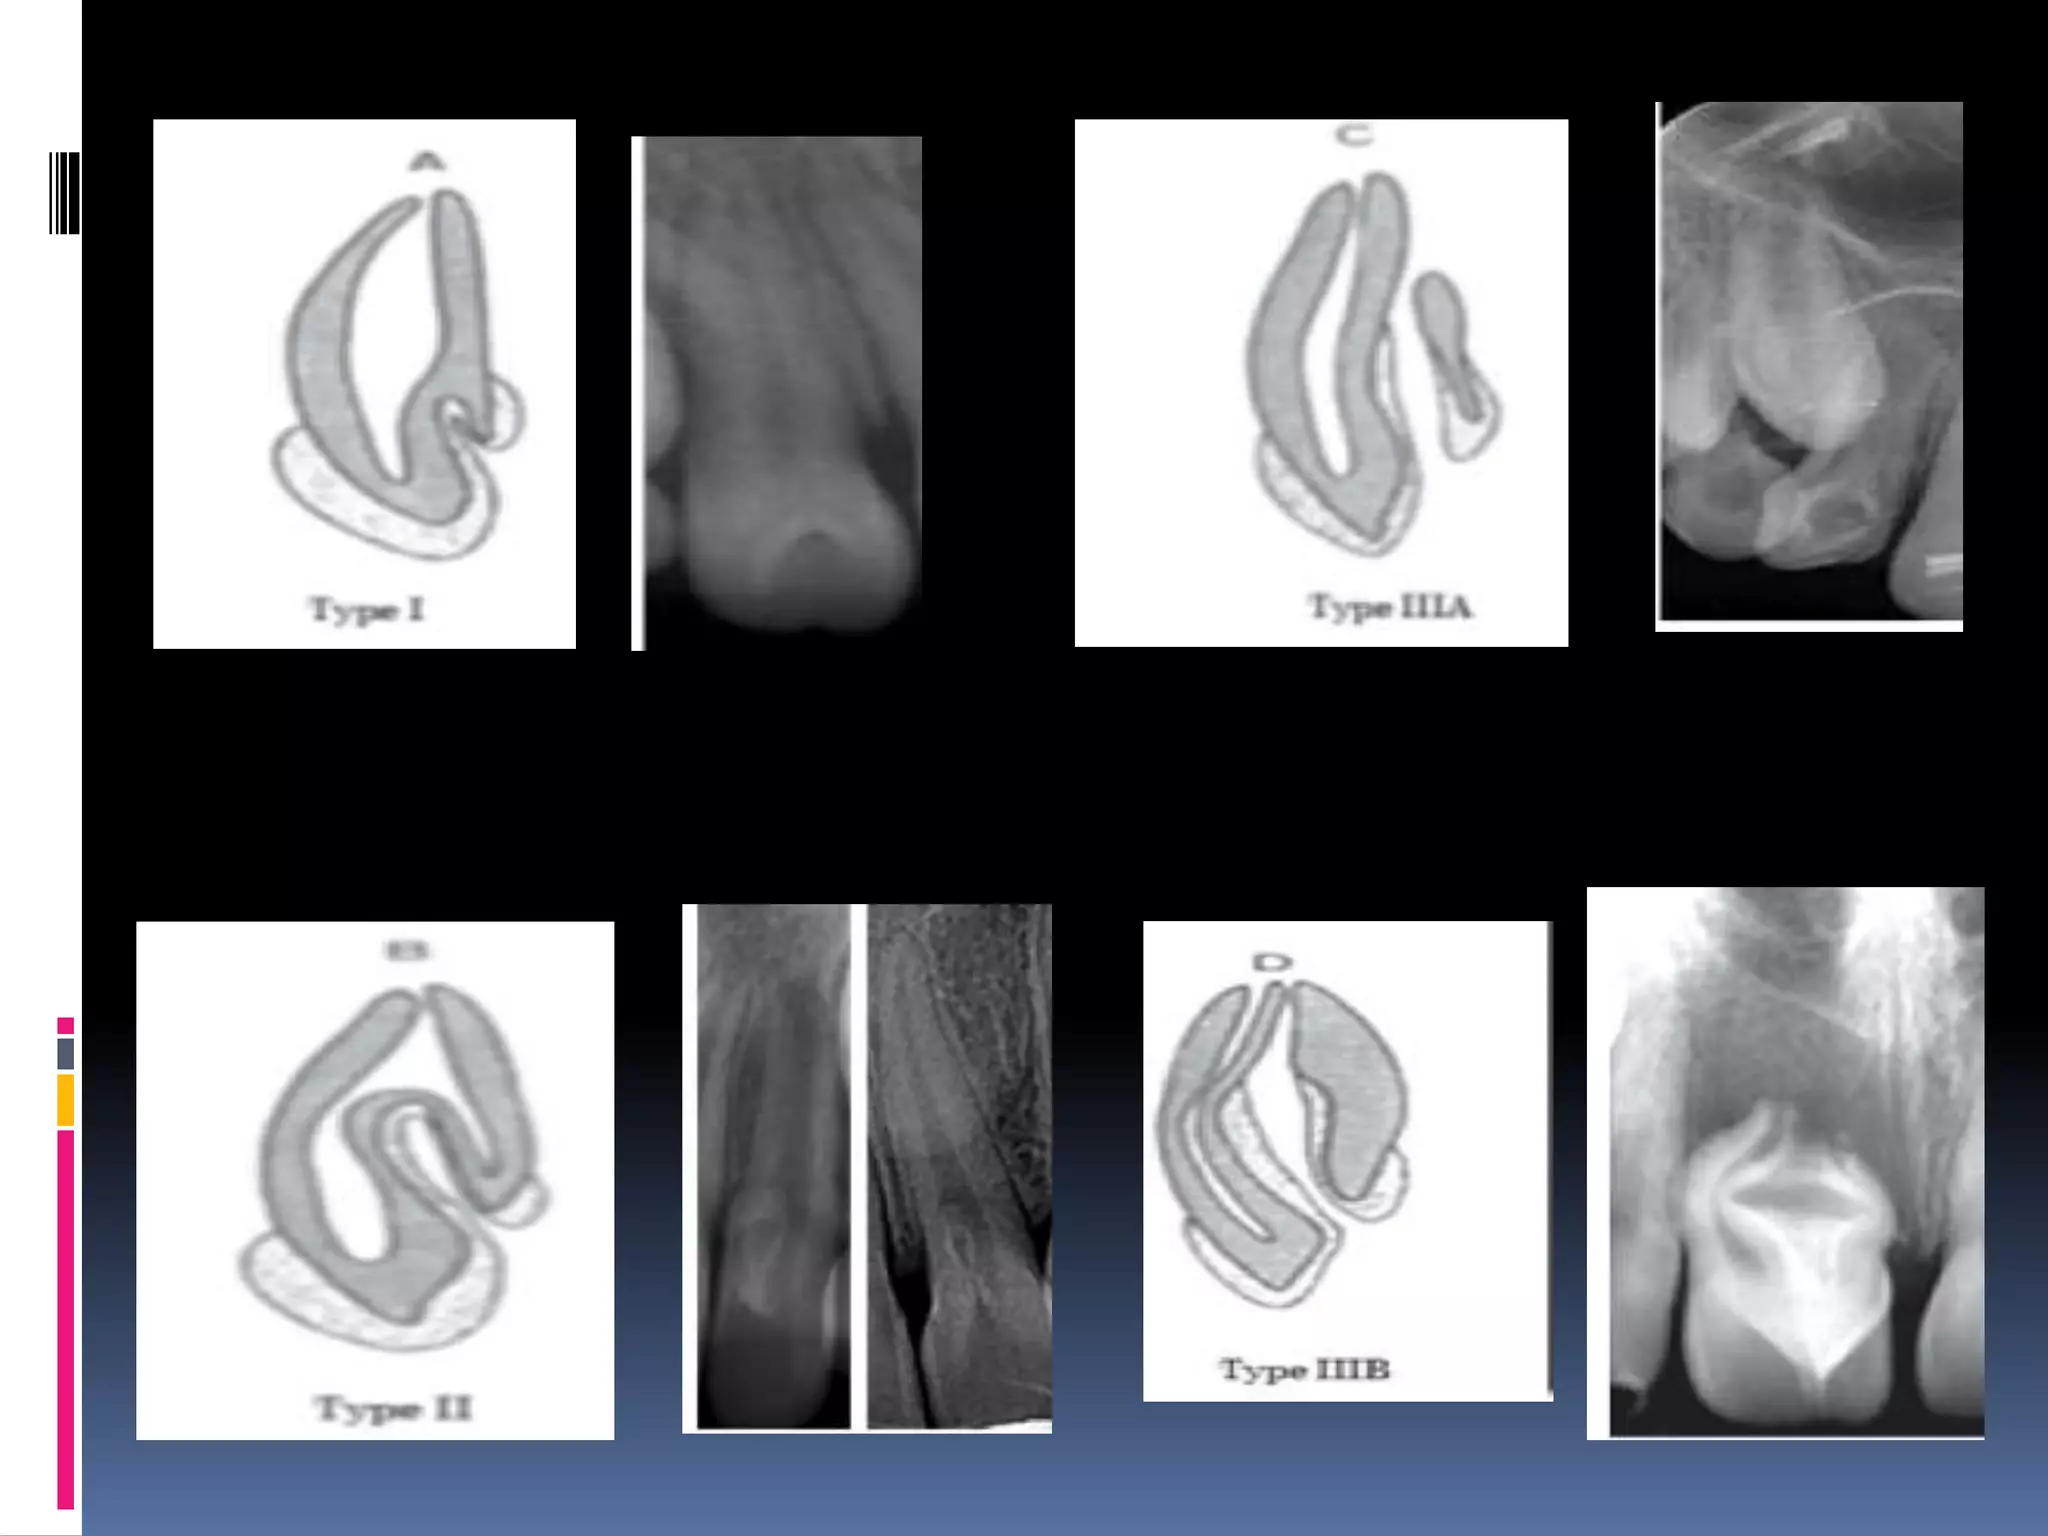

Dens invaginatus/dens

indente

A deep surface invagination of crown/root

lined by enamel.

Due to invagination of surface of tooth crown

before calcification occurred.

 > max laterals

 i)coronal dens invaginatus:

 Type I – invagination confined to crown.

 Type II – extends below CEJ but not

communicating with pulp.

Type III – extends through root & perforate

apical / lateral radicular area.

 Tooth with in tooth